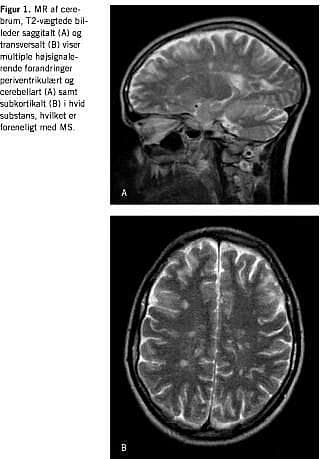

Akut neurologisk blev patienten udredt med CT af cerebrum to gange, hvilket ud over cerebellar atrofi intet abnormt viste. Der blev foretaget spinalvæskeundersøgelse, hvor der fandtes normalt celletal, normalt spinalprotein og -glukose og ingen xantokromi. Som led i den videre neurologiske udredning blev der foretaget MR-skanning af cerebrum, hvilket viste multiple white-matter-lesions periventrikulært, subkortikalt og infratentorialt, hvilket er foreneligt med MS (Figur 1 ). En supplerende spinalvæskeundersøgelse viste forhøjet IgG-indeks og tydelig oligokloni. Visual evoked potentials (VEP) var med normale VEP-latenser bilateralt.